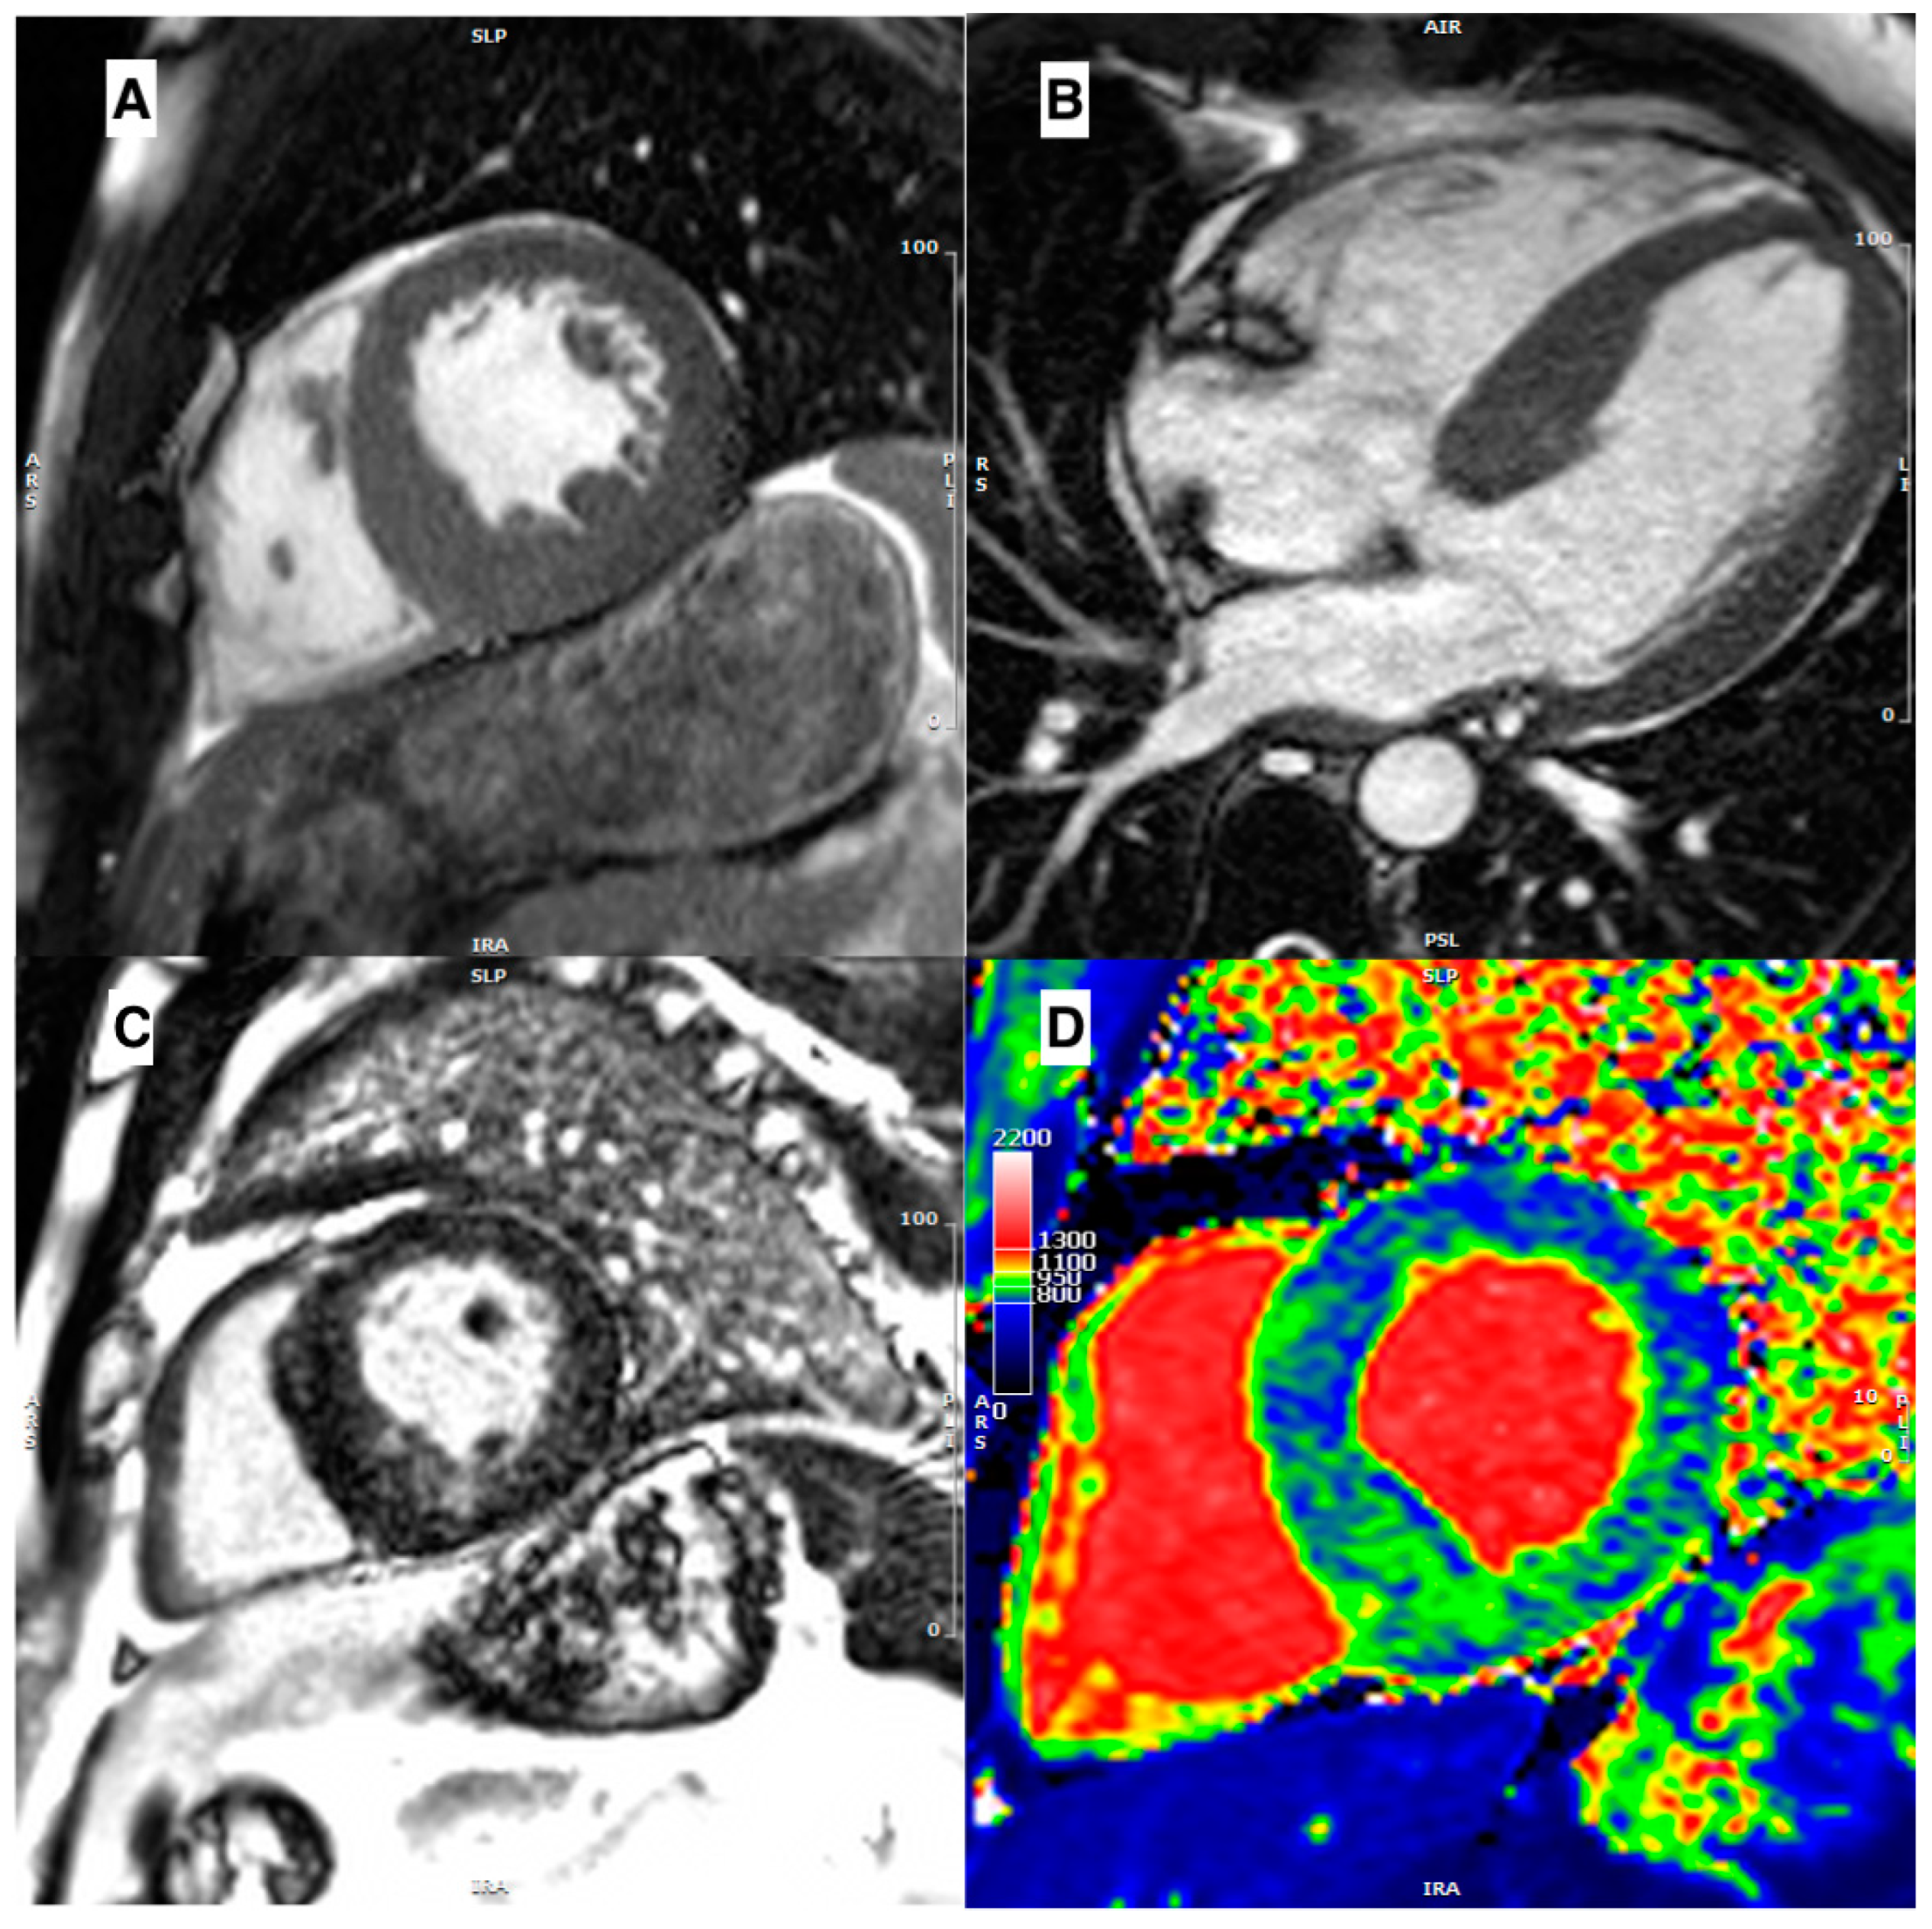

3.3. Role of Late Gadolinium Enhancement

- Mahrholdt, H.; Wagner, A.; Judd, R.M.; Sechtem, U.; Kim, R.J. Delayed enhancement cardiovascular magnetic resonance assessment of non-ischaemic cardiomyopathies. Eur. Heart J. 2005, 26, 1461–1474. [Google Scholar] [CrossRef]

- Moon, J.C.C.; Reed, E.; Sheppard, M.N.; Elkington, A.G.; Ho, S.Y.; Burke, M.; Petrou, M.; Pennell, D.J. The histologic basis of late gadolinium enhancement cardiovascular magnetic resonance in hypertrophic cardiomyopathy. J. Am. Coll. Cardiol. 2004, 43, 2260–2264. [Google Scholar] [CrossRef]

- Yang, K.; Song, Y.-Y.; Chen, X.-Y.; Wang, J.-X.; Li, L.; Yin, G.; Zheng, Y.-C.; Wei, M.-D.; Lu, M.-J.; Zhao, S.-H. Apical hypertrophic cardiomyopathy with left ventricular apical aneurysm: Prevalence, cardiac magnetic resonance characteristics, and prognosis. Eur. Heart J.—Cardiovasc. Imaging 2020, 21, 1341–1350. [Google Scholar] [CrossRef]

- Habib, M.; Adler, A.; Fardfini, K.; Hoss, S.; Hanneman, K.; Rowin, E.J.; Maron, M.S.; Maron, B.J.; Rakowski, H.; Chan, R.H. Progression of Myocardial Fibrosis in Hypertrophic Cardiomyopathy. JACC Cardiovasc. Imaging 2021, 14, 947–958. [Google Scholar] [CrossRef]

- Maceira, A.M.; Joshi, J.; Prasad, S.K.; Moon, J.C.; Perugini, E.; Harding, I.; Sheppard, M.N.; Poole-Wilson, P.A.; Hawkins, P.N.; Pennell, D.J. Cardiovascular Magnetic Resonance in Cardiac Amyloidosis. Circulation 2005, 111, 186–193. [Google Scholar] [CrossRef]

- Moon, J.C.; Sachdev, B.; Elkington, A.G.; McKenna, W.J.; Mehta, A.; Pennell, D.J.; Leed, P.J.; Elliott, P.M. Gadolinium enhanced cardiovascular magnetic resonance in Anderson-Fabry disease Evidence for a disease specific abnormality of the myocardial interstitium. Eur. Heart J. 2003, 24, 2151–2155. [Google Scholar] [CrossRef] [PubMed]

- Maron, M.S.; Appelbaum, E.; Harrigan, C.J.; Buros, J.; Gibson, C.M.; Hanna, C.; Lesser, J.R.; Udelson, J.E.; Manning, W.J.; Maron, B.J. Clinical Profile and Significance of Delayed Enhancement in Hypertrophic Cardiomyopathy. Circ. Heart Fail. 2008, 1, 184–191. [Google Scholar] [CrossRef] [PubMed]

- Bruder, O.; Wagner, A.; Jensen, C.J.; Schneider, S.; Ong, P.; Kispert, E.-M.; Nassenstein, K.; Schlosser, T.; Sabin, G.V.; Sechtem, U.; et al. Myocardial Scar Visualized by Cardiovascular Magnetic Resonance Imaging Predicts Major Adverse Events in Patients With Hypertrophic Cardiomyopathy. J. Am. Coll. Cardiol. 2010, 56, 875–887. [Google Scholar] [CrossRef] [PubMed]

- Chan, R.H.; Maron, B.J.; Olivotto, I.; Pencina, M.J.; Assenza, G.E.; Haas, T.; Lesser, J.R.; Gruner, C.; Crean, A.M.; Rakowski, H.; et al. Prognostic Value of Quantitative Contrast-Enhanced Cardiovascular Magnetic Resonance for the Evaluation of Sudden Death Risk in Patients With Hypertrophic Cardiomyopathy. Circulation 2014, 130, 484–495. [Google Scholar] [CrossRef]

- Todiere, G.; Nugara, C.; Gentile, G.; Negri, F.; Bianco, F.; Falletta, C.; Novo, G.; Di Bella, G.; De Caterina, R.; Zachara, E.; et al. Prognostic Role of Late Gadolinium Enhancement in Patients With Hypertrophic Cardiomyopathy and Low-to-Intermediate Sudden Cardiac Death Risk Score. Am. J. Cardiol. 2019, 124, 1286–1292. [Google Scholar] [CrossRef]

| Disease | Morphological Features | Late Gadolinium Enhancement | Myocardial T1 | ECV |

|---|---|---|---|---|

| Sarcomeric HCM, Pediatric HCM | Several different patterns of hypertrophy Apical aneurysm Crypts Papillary\mitral abnormalities SAM\LVOT obstruction | Mid-wall in hypertrophied segments | Increased only in fibrotic areas | Increased only in fibrotic areas |

| Amyloidosis | Concentrical pseudo-hypertrophy Thickened LA wall Pericardial effusion | Low-difference signal intensity blood-cavity Diffuse subendocardial | Diffusely increased | Diffusely increased |

| Fabry disease | Diffuse hypertrophy (80%), asymmetrical | Inferolateral mid-wall (only in late stage) | Diffusely decreased (increased in LGE areas) | Diffusely decreased (increased in LGE areas) |

| Hypertensive heart disease | Usually, concentric hypertrophy with wall thickness not exceeding 16 mm Rarely, SAM/LVOT obstruction | No LGE | Normal or slightly increased | Normal or slightly increased |

| Mitochondrial cytopathies | Asymmetric (septal) or concentric hypertrophy | Mid-wall LGE in the inferolateral wall or extending in the majority of myocardial segments | Increased, particularly in segments with LGE | Increased, particularly in segments with LGE |

| Glycogen storage disorders | Diffuse or focal myocardial hypertrophy | Patchy mid-wall LGE in septum and insertion point or extending diffusely | Increased | Increased |